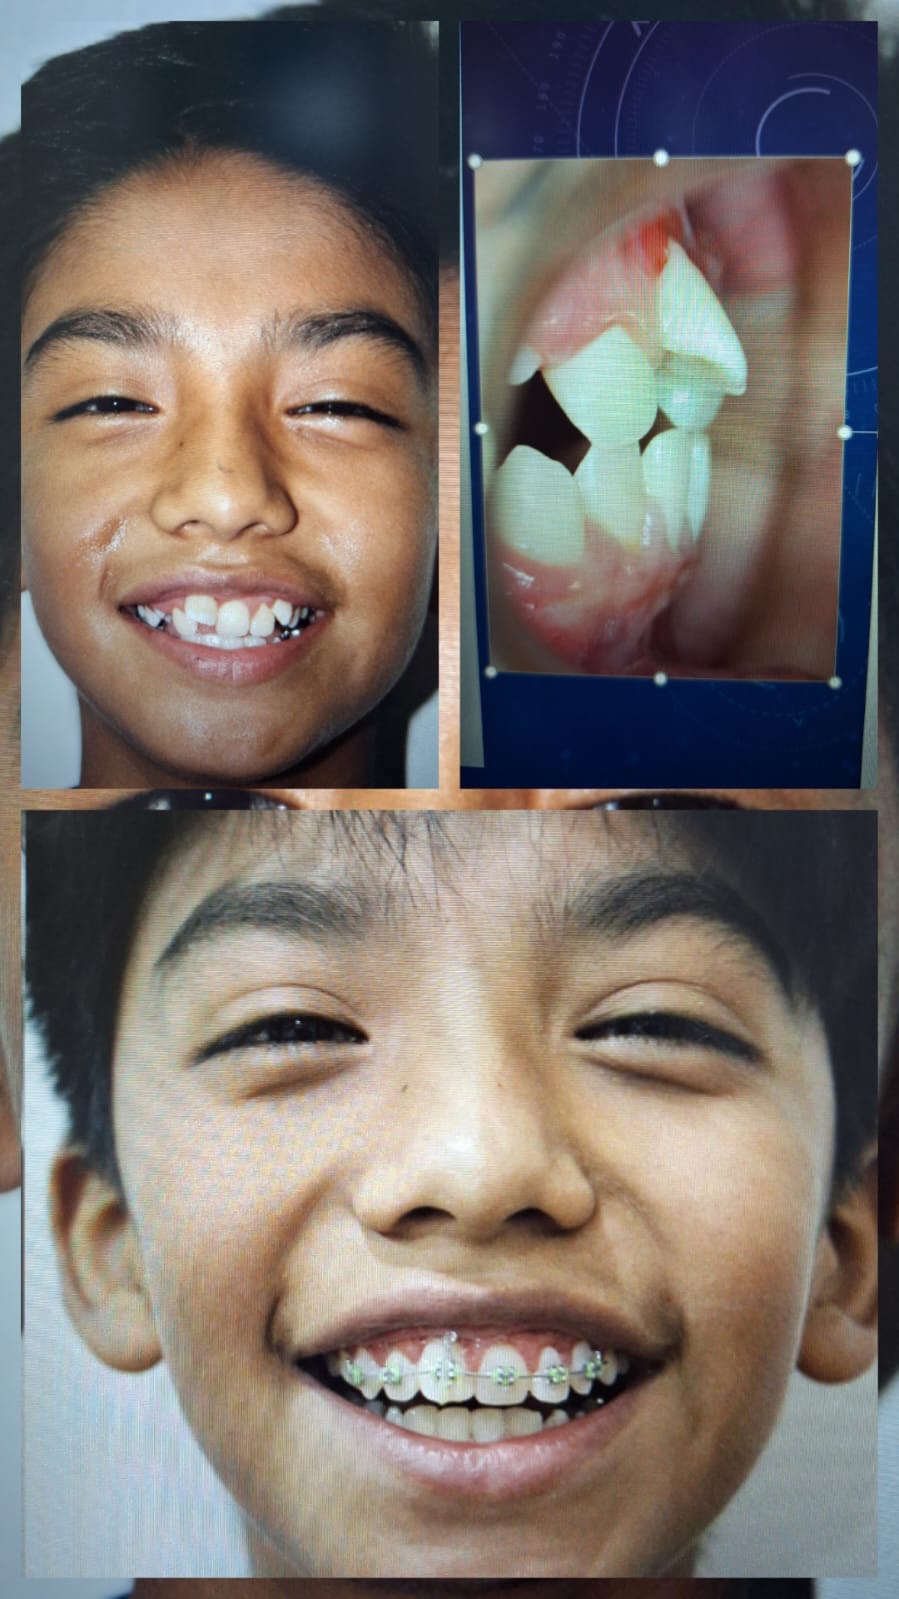

Ortodoncia

Especialistas en alineación y corrección dental, para una sonrisa perfecta.

Odontología Infantil

Cuidado especializado con un enfoque paciente y cercano para que los más pequeños se sientan seguros.

- Tratamientos preventivos y correctivos para niños.

- Ortodoncia interceptiva y funcional.

- Ortopedia maxilar integral para el desarrollo correcto de la mordida.

Nuestra Clínica en Imágenes

Visualiza nuestro compromiso y acompañamiento en cada tratamiento.